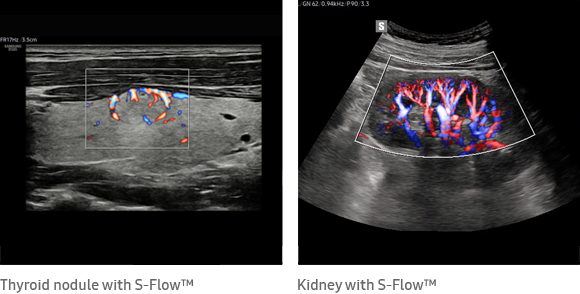

多維度的成像技術為RS85 Prestige帶來眾多功能,如ShadowHDR技術能夠選擇性地應用高頻或低頻超聲波來識別發生衰減的陰影區域;LumiFlow血流視覺化技術,使其更直觀地識別血管的位置;S-Flow則透過定向能量多普勒技術檢查血管外周,獲取血流強度及方向的資訊。